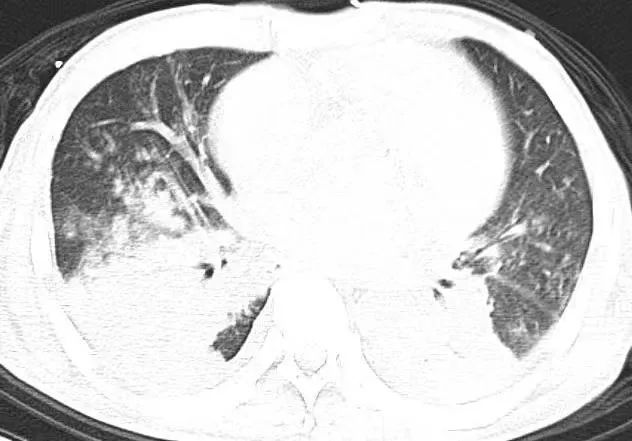

(第一次胸部CT)

第二天,为了解患者肺部状况,重症医学科医生孙前进建议患者查胸部CT,即使心里早有预感,还是大吃一惊!这肺部,简直可以用一塌糊涂来形容:双肺严重感染、双侧胸膜腔积液、双下肺局限性肺不张。尽管入院前无明确受凉史,无明显咳嗽、咳痰,但结合胸部影像学,肺部感染成立。查明原因后,孙医生继续给患者实施呼吸机辅助通气,同时进行抗感染、抗心衰对症用药,继续床旁透析,并输入两袋红细胞纠正贫血,提高携氧能力。